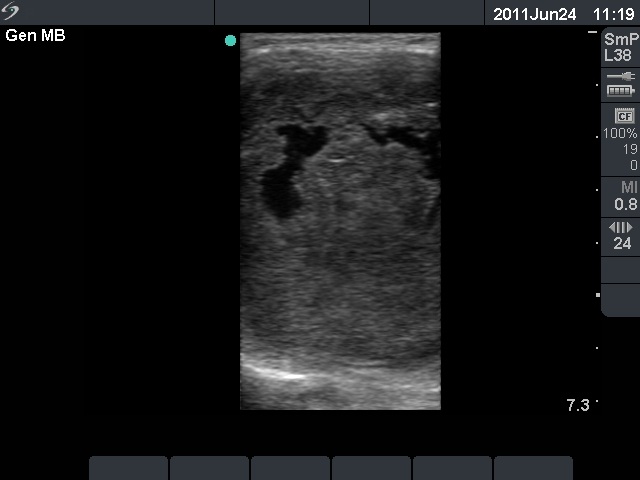

Anaplastic carcinoma - Case 10. |

Clinical data: a 75-year-old woman was referred for an evaluation of a progressive thyroid enlargement. The patient was operated on benign nodular goiter 50 years earlier. She told that her thyroid was enlarged just after the operation but caused no complaints. She noticed a sudden increase in the last two months, which caused dyspnea and dysphagia.

Palpation: a very hard, almost fixed left thyroid.

Ultrasonography: an extremely enlarged left thyroid which was composed of multiple hypoechogenic nodules. The dimensions of the left lobe were 150x180x350 mm.

Cytological report: anaplastic cancer.

Histopathology: anaplastic cancer.